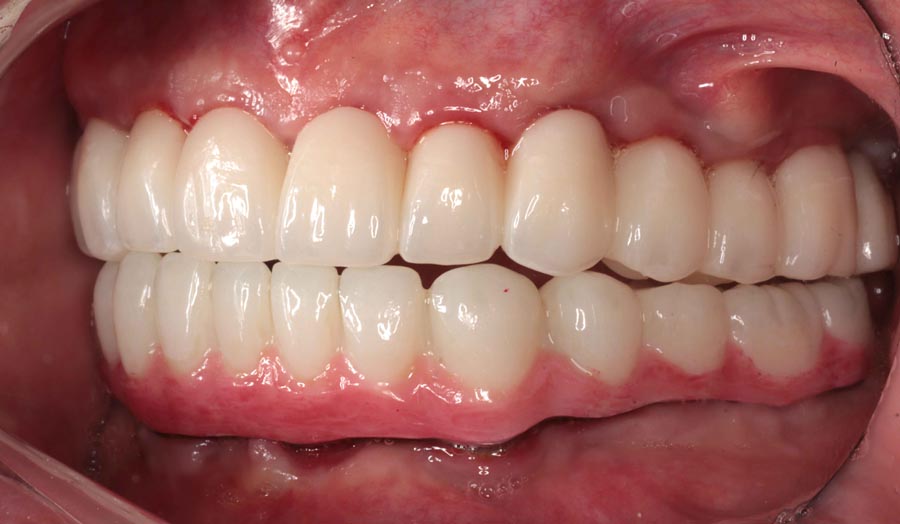

Final prostheses, intraoral, frontal. Homecare is still a problem. The final restorations are much kinder to the tissues and we hope this will resolve some of the inflammation.